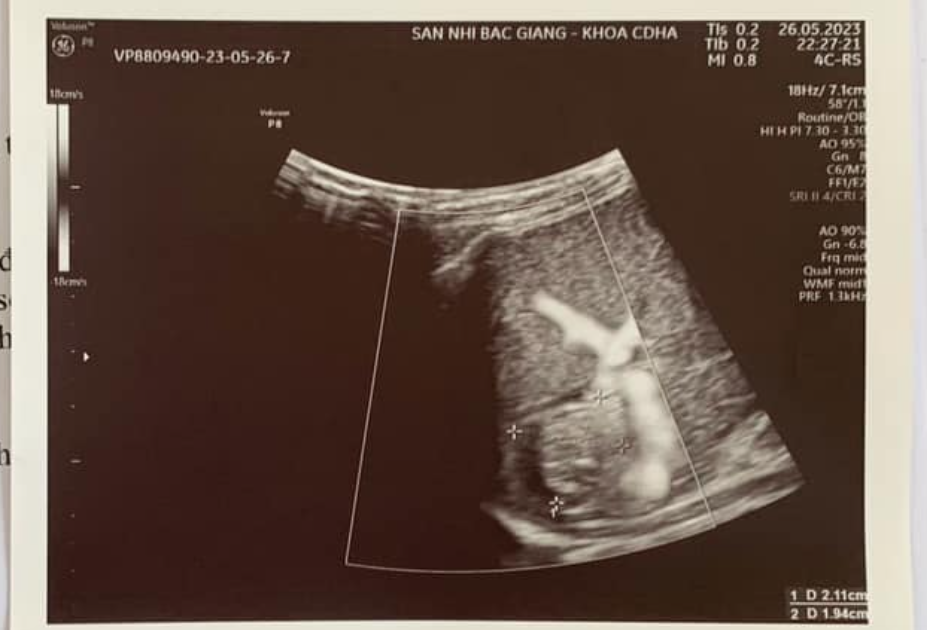

Ngay khi nhập viện, Minh Khôi được các bác sĩ Khoa Ngoại thăm khám lâm sàng và nhận thấy các chỉ số sinh tồn không ổn định: mạch nhanh, huyết áp thấp, da niêm mạc tái. Bụng trẻ chướng, nắn đau khắp bụng, đau nhiều vùng mạn sườn trái, phản ứng thành bụng rõ. Siêu âm ổ bụng phát hiện có nhiều dịch tự do ổ bụng và hình ảnh đường vỡ lách khá rõ. Với chẩn đoán trẻ bị vỡ lách trong chấn thương bụng kín, các bác sĩ đã chỉ định làm các xét nghiệm cấp cứu cần thiết đồng thời chuyển bệnh nhi lên Phòng phẫu thuật và sẵn sàng truyền máu trong khi phẫu thuật để đảm bảo an toàn tính mạng cho trẻ.